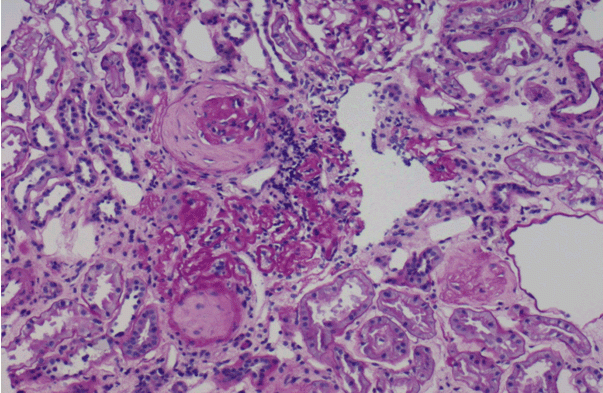

(그림 2)33세 여자 환자로 소변검사는 거의 정상이었으나 여과율이 55ml/min으로 저하된 환자에게 신장조직검사를 시행한 결과, IgA 신장염 5기로 진단된 경우도 있었다.